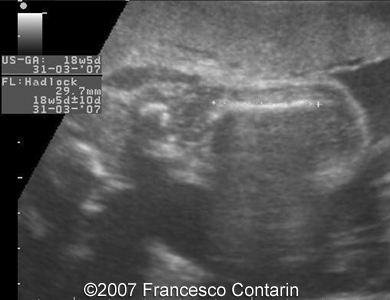

This is a 22-year-old woman (G4, P2) with unremarkable familiar history, referred to our hospital at 29 weeks of gestation due to a fetal ascites. There were no signs of maternal-fetal blood incompatibility. The ultrasound investigation revealed rhizomelia, postaxial polydactyly, small thorax, short ribs, ascites, increased abdominal biometric parameters, polyhydramnios. We supposed two diagnoses: Short rib-polydactyly syndrome versus Jeune syndrome (asphyxiating thoracic dystrophy).

Images 15. 29th week of pregnancy -  transverse plane through fetal pelvis - wide iliac wings.

15